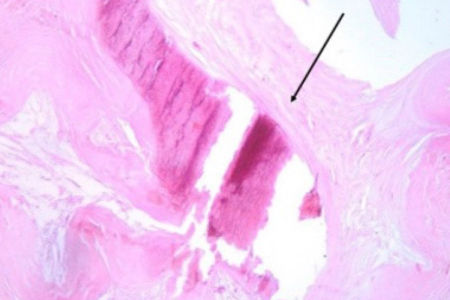

Le microcalcificazioni, piccoli depositi di calcio che si formano nel tessuto mammario e che possono essere rilevati alla mammografia, sono spesso, ma non sempre, un segnale di allarme per la presenza di un tumore al seno. E la relazione fra microcalcificazioni e tumore non è stata mai chiarita.

I ricercatori hanno infatti scoperto infatti che la relazione tra le microcalcificazioni e il tumore è legata alla presenza di un particolare minerale chiamato whitlockite, che è ricco di magnesio e che si trova nelle microcalcificazioni solo in assenza del tumore. I ricercatori hanno usato tecniche avanzate di spettroscopia (Raman, WAXS, XRF), per analizzare le microcalcificazioni prelevate da pazienti affette da tumore al seno. Hanno confrontato i campioni con quelli di donne sane e hanno osservato che nei tessuti tumorali la whitlockite era quasi assente, mentre nei tessuti sani era abbondante.

Questo suggerisce che il tumore al seno ha la capacità di alterare il metabolismo del calcio e del magnesio nel tessuto mammario, influenzando la formazione delle microcalcificazioni, eliminando la whitlockite e rendendole più dure, cosa che le rende in grado di stimolare ancora di più la crescita del tumore.